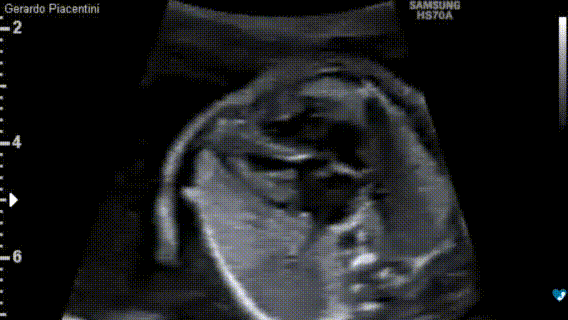

Ecocardiografia fetale - 17 settimane

Ecocardiografia fetale - 22 settimane